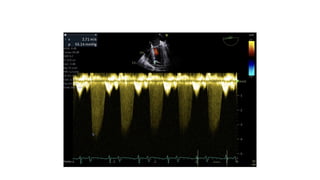

TTE

• LV-51/40

• IVS- 8/7

• EF-30%

• LA-31

• AO-29

• RWMA- AL/AW/Apex- Akinetic

• Apical VSR-4mm with L-R shunt (multiple fenestration

present), gradient-60mmHg

• Moderate RV dysfunction (TAPSE-11)

• MR 2+

• Moderate- severe LV Dysfunction